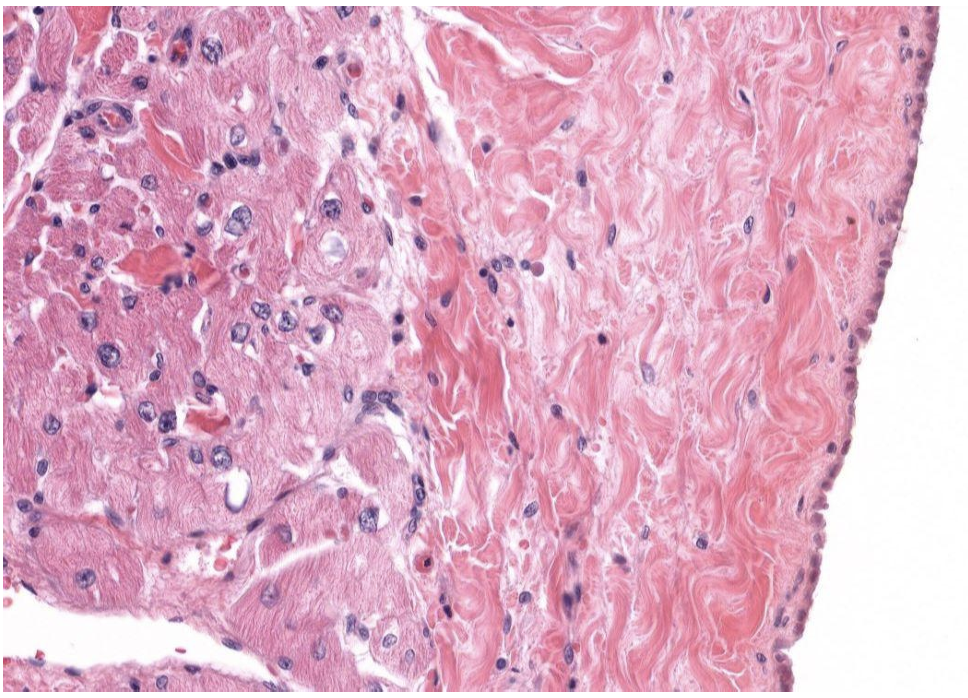

Identify Which partition this is and Where?

I = Epicardium (right side) and Myocardium (Left) in Atrium.

Outer mesothelial (simple squam epit), supported by DICT.